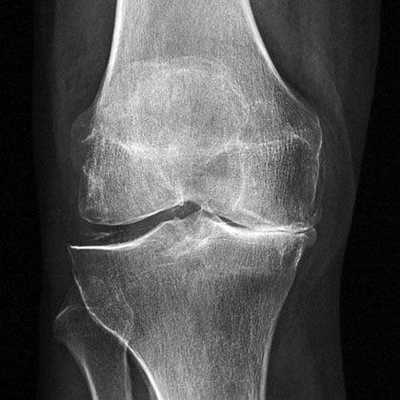

Артроз коленного сустава на рентгене.

Показания к замене

Посмотрите на рентген, на нем вы видите, до какой степени при запущенном гонартрозе изношен гиалиновый хрящ, обеспечивающий гладкое скольжение суставных поверхностей. Концевые участки костей грубо деформируются нарушая функции сгибания и разгибания конечности вызывая интенсивный болевой синдром.

Динамика болезни на рентгене.